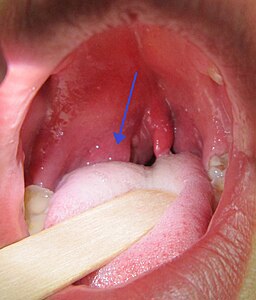

Quinsy

James Heilman,MD, CC BY-SA 3.0 https://creativecommons.org/licenses/by-sa/3.0, via Wikimedia Commons https://commons.wikimedia.org/wiki/File:PeritonsilarAbsess.jpg